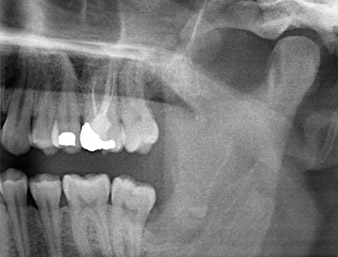

Seis meses después de una osteotomía del diente 38, un paciente de 26 años padecía dolores repetitivos en la zona de la operación y se quejaba de hipersensibilidad en la zona de extensión del nervio alveolar inferior. El odontólogo que lo remitió, y que no era quien había realizado la extracción dental original, lo envió al departamento de cirugía oral de la Clínica Dental Universitaria de Viena.

Ya en la ortopantomografía, se constató que había un resto radicular de la región 38 muy cerca del nervio alveolar inferior (figura 1). La raíz se había fracturado durante la osteotomía, pero el primer odontólogo que había tratado al paciente no había extraído esta debido a la presencia de dolor durante la operación.

Ortopantomografía

Imagen 1: Ortopantomografía 6 meses después de la osteotomía del diente 38: el resto radicular se encontraba cerca del nervio alveolar inferior.

La anamnesis del paciente era favorable (no fumador, 26 años) para garantizar el éxito de la aplicación. Como la ortopantomografía mostró que el resto radicular se encontraba muy cerca del nervio alveolar inferior, se realizó también una tomografía volumétrica digital (6).